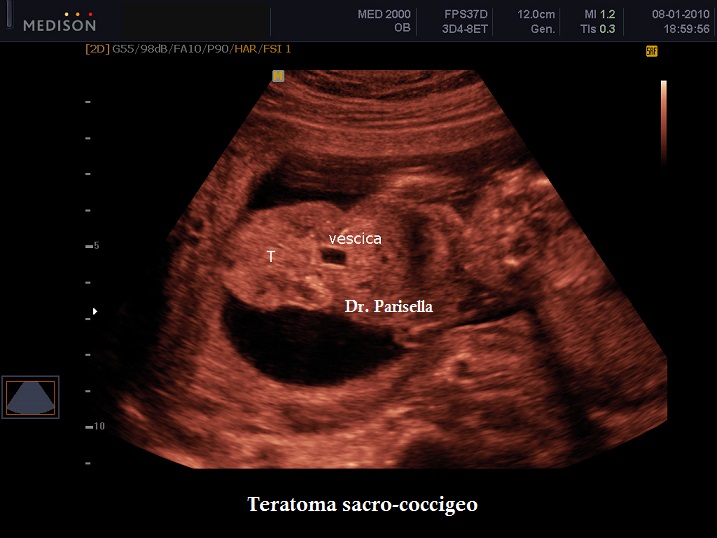

Dal punto di vista ecografico si presenta come una massa esofitica ad origine dalla regione sacrale, ad aspetto di tipo solido o complex nell'85% dei casi o di tipo cistico nel 15% dei casi; nel 35% dei casi sono presenti delle calcificazioni.

Importante è lo studio della vascolarizzazione della massa: il riscontro di una vascolarizzazione elevata è caratteristico delle masse più voluminose ed a crescita rapida, mentre una vascolarizzazione assente o modesta si riscontra nelle masse cistiche e in quelle meno voluminose ed a crescita lenta. La vascolarizzazione inoltre, può creare uno shunt ad alta gittata che a sua volta può essere responsabile dell'insorgere di un Idrope Fetale.